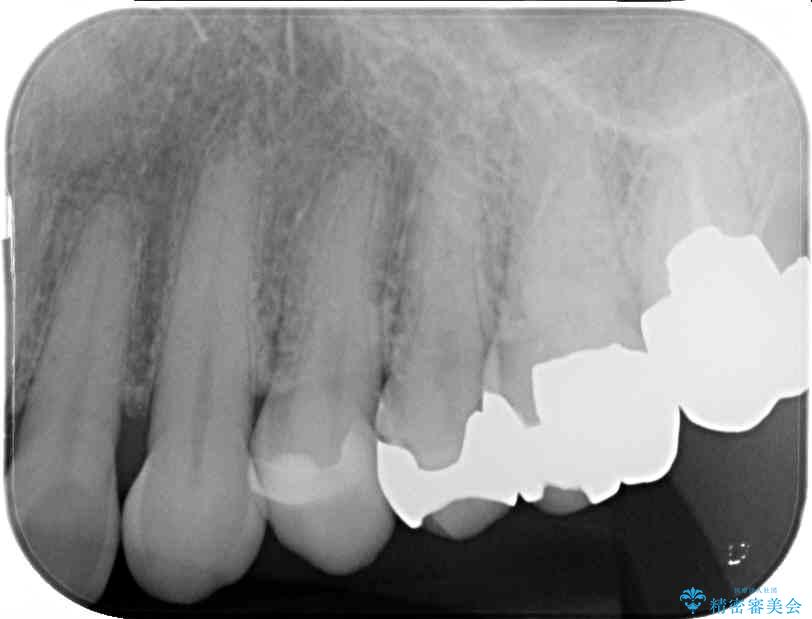

奥歯の銀歯が外れてしまったため、セラミック治療を希望された患者様です。

治療前

• 外れてしまった銀歯 セラミックインレーで自然な仕上がりに 治療前画像